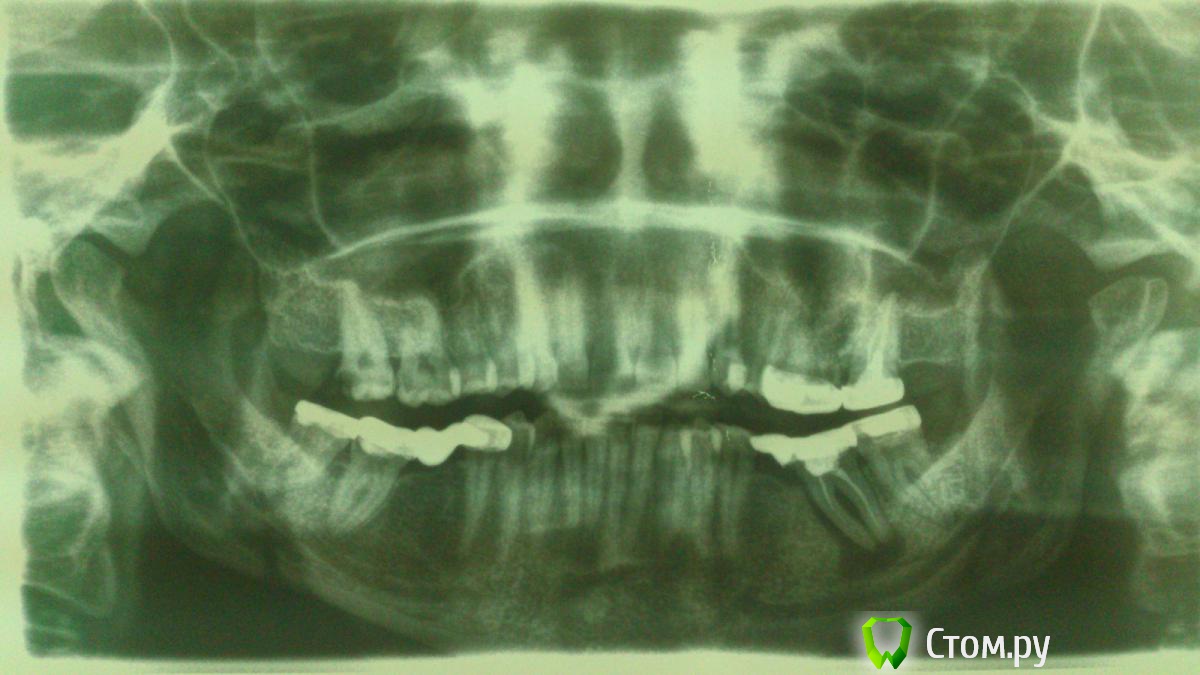

SanderS Опубликовано 28 октября, 2014 Поделиться Опубликовано 28 октября, 2014 (изменено) Пришла пациентка, жалобы на периодически ноющие боли слева НЧ, немного подвижен мост 3.7-3.8. Прогноз? Мосту 4 года, кармана по медиальной стенке не нащупал Изменено 28 октября, 2014 пользователем SanderS Ссылка на комментарий

SanderS Опубликовано 28 октября, 2014 Автор Поделиться Опубликовано 28 октября, 2014 Убрать консоль,эндо,полугодичный рекол.Ну собственно я так пациентке и сказал. Шеф сказал там киста ( смотри размеры!!!) - удалять, не в первый раз мнения расходятся. Ссылка на комментарий

Гарриевич Опубликовано 28 октября, 2014 Поделиться Опубликовано 28 октября, 2014 перегруз еще устранить нужно Ссылка на комментарий